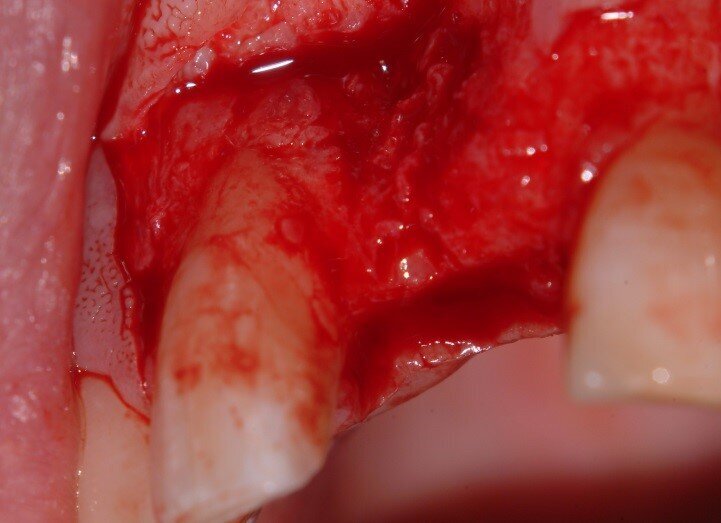

2. Extraction and the split root confirmed (Fig. 4)